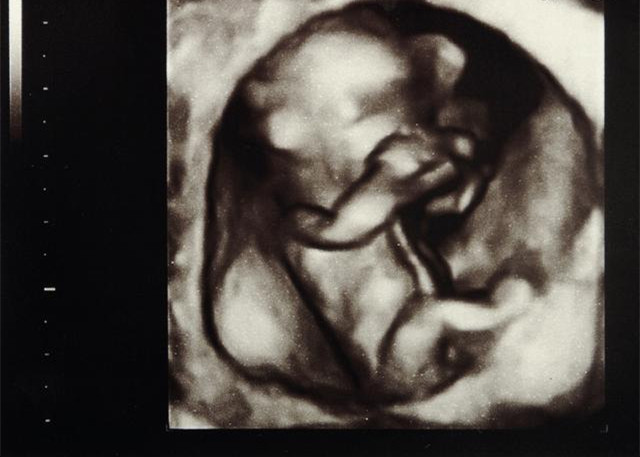

孕7周胎儿孕7周胎儿尾巴已经逐渐缩短,突起的鼻子已经在一张一合地运动,能很清楚地看到小黑点一样的眼睛和鼻孔。胎儿的身体也发生了变化,头部将移动到脊椎上面,而且尾巴也逐渐缩短。手臂和腿部明显变长、变宽,所以容易区分手臂和腿部,还能分辨出手和肩膀。

孕8周胎儿

此时已经完全可以区分出手臂和腿,而且胎儿的长度也有很大变化,手指和脚趾也成形了。此时胎儿的皮肤薄而透明,能清晰地看到胎儿的血管,胎儿的脸部形成了眼皮,开始显露出胎儿的鼻子和嘴唇,同时开始形成睾X丸或卵X巢生X殖器组织。